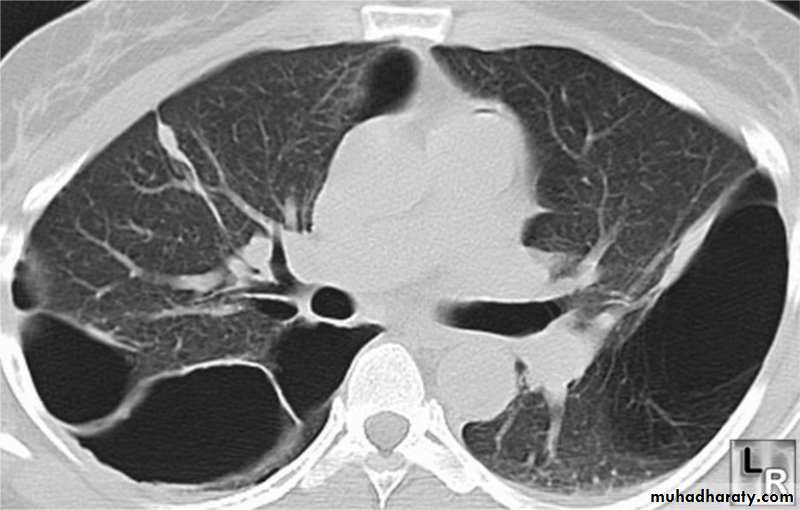

High resolution CT scan (HRCT) is the definitive test to exclude the diagnosis of emphysema. However, this is only required when planning for surgeryInvestigations